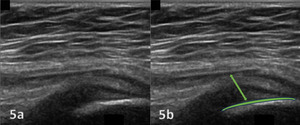

The evaluation of the gluteus medius tendon with MSKUS begins with the patient in a lateral decubitus or standing position, targeting the lateral aspect of the hip. The normal gluteus medius tendon appears as a fan shaped fibrillar structure composed of hyperechoic, striated fascicles with bright, linear bands running within the muscle.2 Pathological changes such as tendinopathy are characterized by hypoechoic (darker) regions within the tendon, tendon thickening, and loss of the normal fibrillar pattern. Tears are identified by discontinuity in the tendon fibers, with partial tears showing as anechoic (black) areas and complete tears as a full separation of the tendon from its insertion.